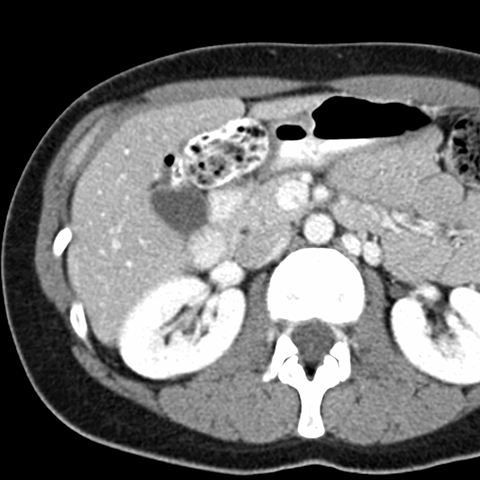

Normal Liver, CT ( axial ) [9 of 9]